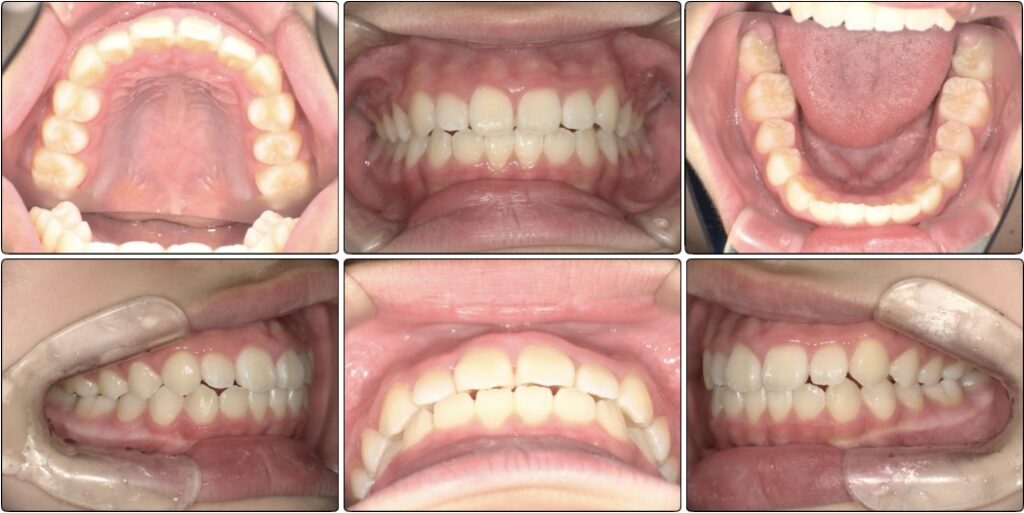

一年後の経過

スタートから一年後の歯並びです。

初めは平坦気味だった2番目の歯もアーチに沿って綺麗になっています。

ですがまだ生え変わりがあることと、スペースに余裕はないため装置を装着しました。

歯と歯にしっかりと隙間ができて広がっています。

装置をつけると一時的に出っ歯っぽく見えていますがここからまた上顎は変わっていきます。